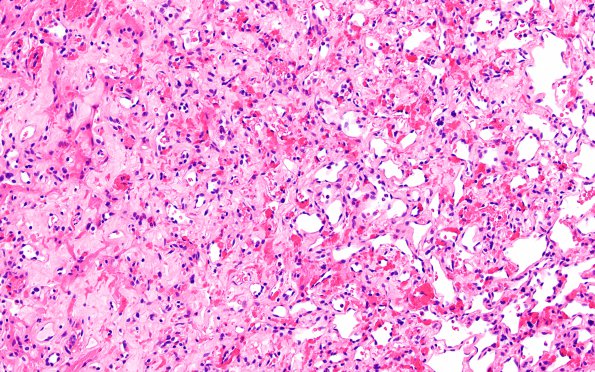

Washington University Experience | NEOPLASMS (MESENCHYMAL, NON-MENINGOTHELIAL) | Hemangioblastoma | 11A2 Hemangioblastoma (Case 11) H&E 20X

A small focus of hemangioblastoma with numerous vessels and vacuolated stromal cells is shown. (H&E)